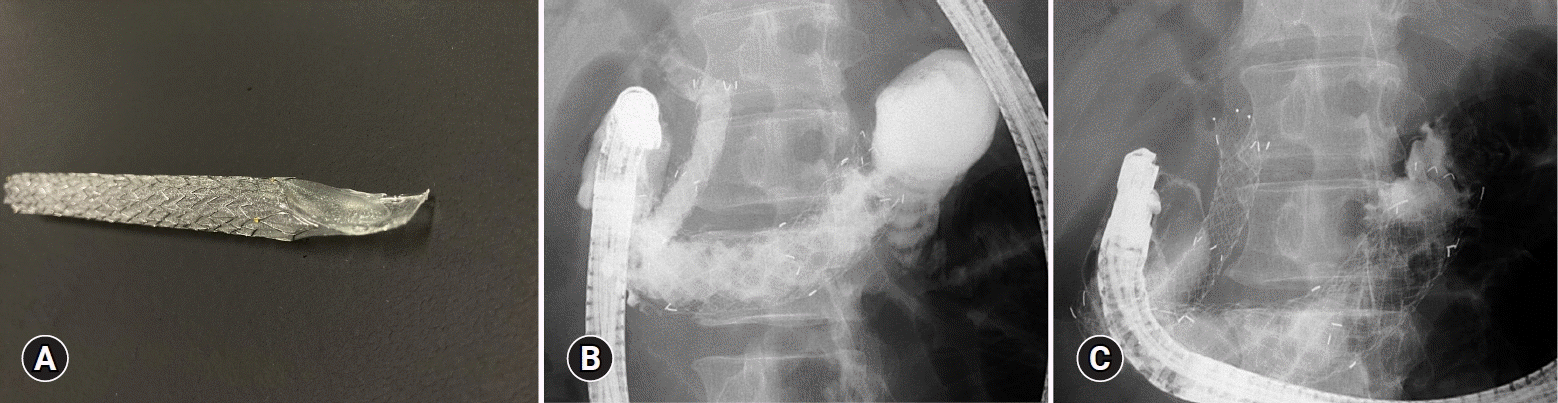

Among braided SEMSs, the Niti-S S-type stent (Taewoong Medical) is a PCSEMS with a 1 cm uncoated portion on the biliary side.56 This stent has a weak hold on the gastrointestinal wall and no antimigrational properties on the luminal side, which may cause delayed migration out of the gastrointestinal tract into the abdominal cavity. To overcome this drawback, modified stents have been developed, such as the Niti-S Spring Stopper Stent (Taewoong Medical) (Fig. 2) and the Hybrid Bonastent (Standard Sci. Tech) and the GIOBOR stent (Taewoong Medical), which has antimigrational properties on the luminal side.57-59 However, the diameter of these SEMS delivery systems is 8.0 to 8.5 Fr, and tract dilatation is usually required during EUS-BD.

Fig. 2.

Endoscopic ultrasound-guided hepaticogastrostomy using the Spring Stopper Stent (Taewoong Medical). (A) Partially braided self-expandable metal stent with a spring-type stopper on the luminal side (Niti-S Spring Stopper Stent; Taewoong Medical). (B) Radiographic image: fistula formation using a Spring Stopper Stent between the intrahepatic bile duct and stomach. (C) Endoscopic view of the Spring Stopper Stent.